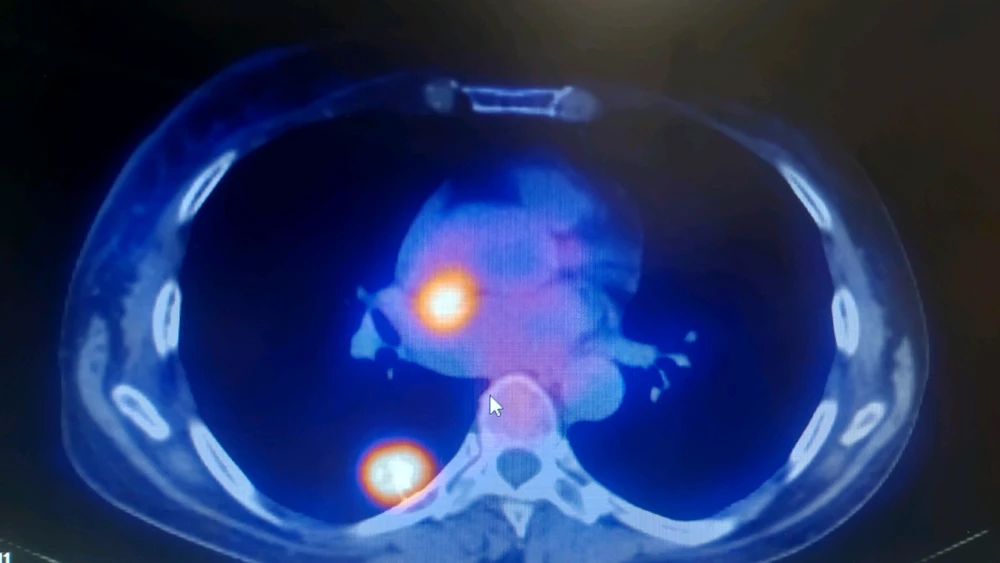

Nodulo pulmonar solitario en segmento superior de lóbulo inferior derecho (LID). A esto en radiología se le puede llamar de varias maneras, por ejemplo condensación pulmonar con bronquio abierto (el puntito negro que se ve en la imagen más blanca) en contacto con pleura (está pegada a pared... leer más